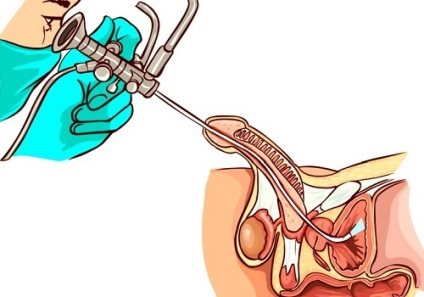

Transuretrala Diagnostics - tehnica invaziva implica introducerea cistoscopul prin uretra

În acest caz, vizualizarea organelor interne folosind undele de ultrasunete va fi foarte dificil, iar rezultatul poate fi distorsionat. În această situație, pacientul este atribuit Trus de prostata, ceea ce presupune introducerea unui senzor special în rect. Această metodă este considerată mai fiabilă, informativ și a recomandat să efectueze la semnele de schimbare in tesutul de prostata.

Metoda cu ultrasunete transabdominala este cea mai comună. Această procedură este sigură și nu produce nici pacienții disconforturi. Datorită ecografie, medicul poate obține informațiile necesare cu privire la starea de prostata si a altor organe pelvine, care pot fi, de asemenea, modificat in boala de prostata. Ultrasunete dezvaluie patologia de organe si diagnosticarea boli ale sistemului genito-urinar. În ciuda comoditatea și confortul tehnica transabdominală, atunci când o suspiciune medic urolog de abateri grave de la nivelul glandei prostatei de sex masculin, se recomandă să se supună transrectală sau studiu transuretrala.